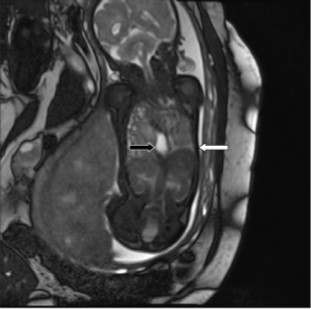

For each patient, the original ultrasound wherein the LHR had been calculated was reviewed, and the U/S LHR noted. A single reviewer (EP) analyzed these ultrasound images to determine the accuracy of of U/S LHR calculation. All practitioners in the Maternal Fetal Medicine department use the same technique for calculating LHR, the longest diameter method15. The images were reviewed to ensure that the cross-sectional area of the contralateral lung was measured at the four chamber view of the heart (Figure 1), the cross-sectional area was calculated with the longest diameter in the correct plane, the width was perpendicular in the correct plane, and the actual calculation was mathematically accurate. The U/S LHR values were then calculated by entering these measurements into the LHR calculator on perinatology.com. The inaccurate calculations were categorized based on the reason for inaccuracy: not measured at the level of the four chamber view of the heart, inaccurate calculation, poor images, no calipers, or oblique angle.

Figure 1.Fetal ultrasound demonstrating apropriate measurement of lung at the four-chamber view of the heart

Fetal ultrasound demonstrating apropriate measurement of lung at the four-chamber view of the heart